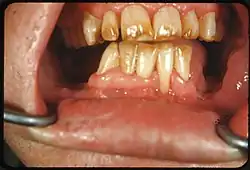

Dental fluorosis appears as a range of visual changes in enamel[4] causing degrees of intrinsic tooth discoloration, and, in some cases, physical damage to the teeth. The severity of the condition is dependent on the dose, duration, and age of the individual during the exposure.[1] The "very mild" (and most common) form of fluorosis, is characterized by small, opaque, "paper white" areas scattered irregularly over the tooth, covering less than 25% of the tooth surface. In the "mild" form of the disease, these mottled patches can involve up to half of the surface area of the teeth. When fluorosis is moderate, all of the surfaces of the teeth are mottled and teeth may be ground down and brown stains frequently "disfigure" the teeth. Severe fluorosis is characterized by brown discoloration and discrete or confluent pitting; brown stains are widespread and teeth often present a corroded-looking appearance.[1]

| Moderate | 4 | All enamel surfaces of the teeth are affected and surfaces subject to attrition show wear. Brown stain is frequently a disfiguring feature |

| Severe | 5 | All enamel surfaces are affected and hypoplasia is so marked that the general form of the tooth may be affected. The major diagnostic sign of this classification is discrete or confluent pitting. Brown stains are widespread and teeth often present a corroded-like appearance. |